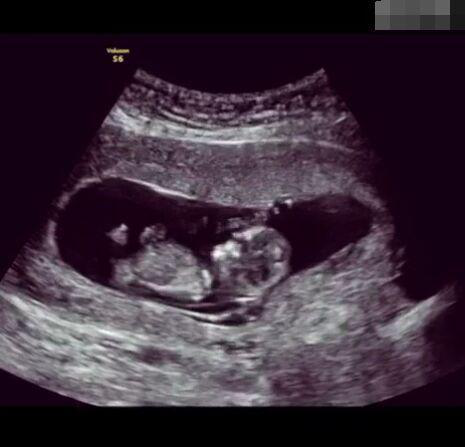

懷孕后,寶寶的性別一直是全家人的重點(diǎn)關(guān)注對象。而男女性別的差異,在基因層面體現在第二十三對染色體上,如果是XY則是男孩,XX則是女孩,這都是由那枚與卵子結合的精子來(lái)決定。

那些做了B超檢查確定胎兒男女,生下來(lái)后發(fā)現不對的,多半是因為在B超檢查時(shí)寶寶太調皮,以致影響了檢查準確性。就比如說(shuō),有的女寶寶在媽媽肚子里玩自己的臍帶,把臍帶夾到了兩腿中間,B超就有一定幾率拍出來(lái)好像是男寶寶的特征,導致被誤認為是男孩子。還有些男寶寶過(guò)分害羞,在做B超時(shí)雙腿緊緊并攏,醫生也很難判斷男女,只好大致猜測是女孩,就又造成了誤會(huì )。因此,B超亦不是萬(wàn)能的。